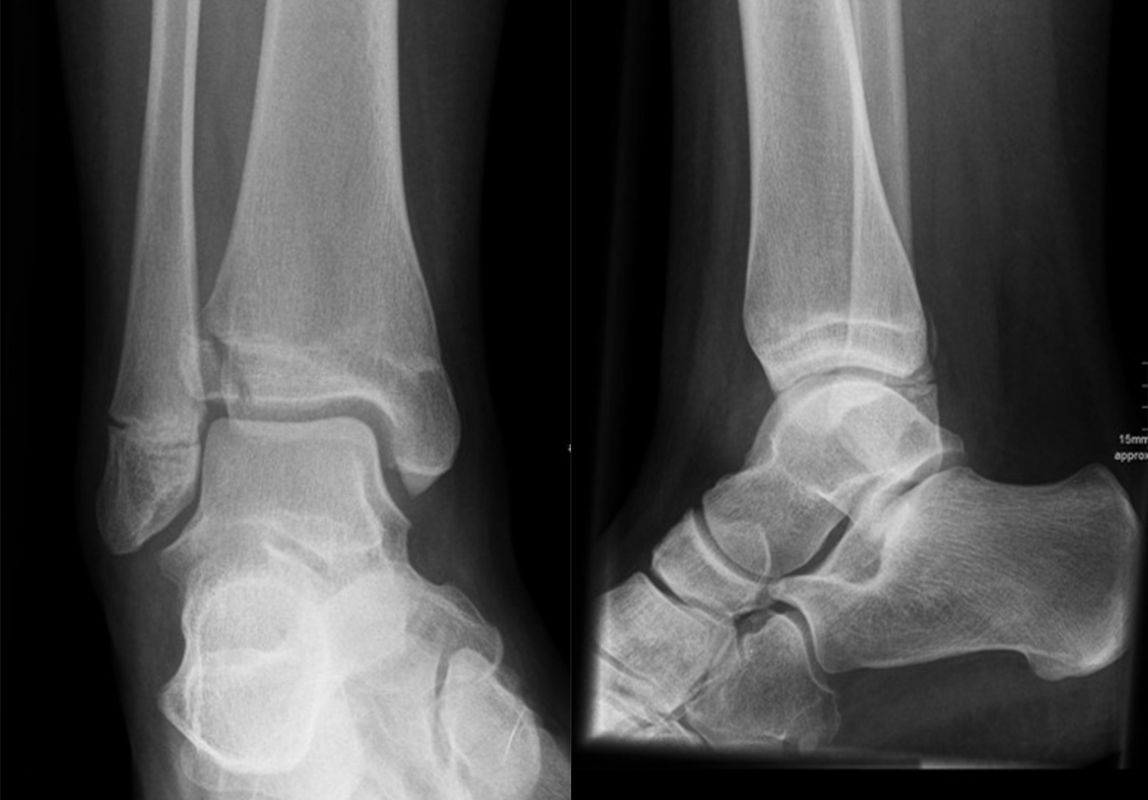

Mediale Malleolarfrakturen

Bei den medialen Malleolarfrakturen handelt es sich um Fugengelenkfrakturen bzw. Aitken II und III Verletzungen. Kennzeichnend ist, dass der Frakturverlauf die wachstumsaktive Zone zur Epiphyse hin durchkreuzt. Die Verletzung der wachstumsaktiven Zone macht diese Verletzungen besonders problematisch.

Fugengelenkfrakturen treten typischerweise vor dem 10. Lebensjahr auf, in einer Phase, in welcher die Wachstumsfugen noch weit offen sind. Dieser Frakturtyp betrifft fast ausschließlich den medialen Malleolus. Laterale Frakturen sind extrem selten, teilweise kommt es zu lateralen Bandverletzungen oder Fugenschaftfrakturen der distalen Fibula. Die Frakturlinie verläuft in einer Verlängerungslinie von der medialen Taluskante nach proximal. Häufig stellen sich Verletzungen des Innenknöchels im Röntgenbild schlechter dar, insbesondere wenn die Aufnahmen verdreht sind oder die Ebene der Fraktur bei geringer Dislokation verkippt zur Röntgenebene liegt. Besteht klinisch der geringste Hinweis auf eine Verletzung des Innenknöchels, muss aufgrund der Tragweite der Verletzung durch entsprechende Aufnahmen gegebenenfalls auch Schnittbildverfahren die Verletzung sicher diagnostiziert oder ausgeschlossen werden (Abb. 15).

Fugengelenkfrakturen können die Wachstumsfuge durchkreuzen (Abbildung 16a), ohne oder nur mit minimaler Beteiligung der Fuge sehr weit medial liegen (Abbildung 16b) oder durch die Fuge auslaufen (Abbildung 16c). Relevant für die Wachstumsprognose ist weniger die Form der Fraktur, sondern das Alter des Patienten zum Zeitpunkt des Traumas sowie das Ausmaß der Schädigung der Wachstumsfuge, wobei eine Korrelation mit dem Ausmaß der Dislokation besteht.